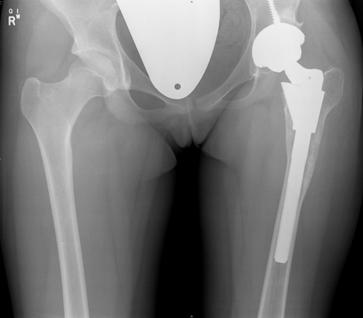

Some hips present with complex deformities. Examples are shown below. These hips often have had previous surgery resulting in severe stiffness or anatomical deformities. Others have significant congenital abnormalities like hip dislocation.

Careful pre-operative planning is done often using the OPS software analysis and an operative plan developed with attention to implant positioning and implant types. Surgery is performed via the posterior approach. Occasionally extra bone graft is required to the pelvis/acetabulum or even femoral bone shortening (in high congenital hip dislocation).

These are examples of complex hip replacements: